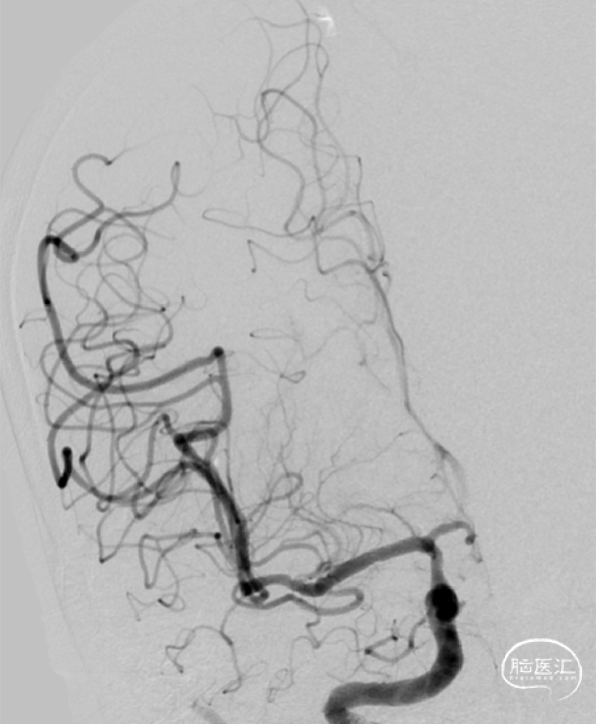

➢DSA(2023.11.10)

术后正侧位。